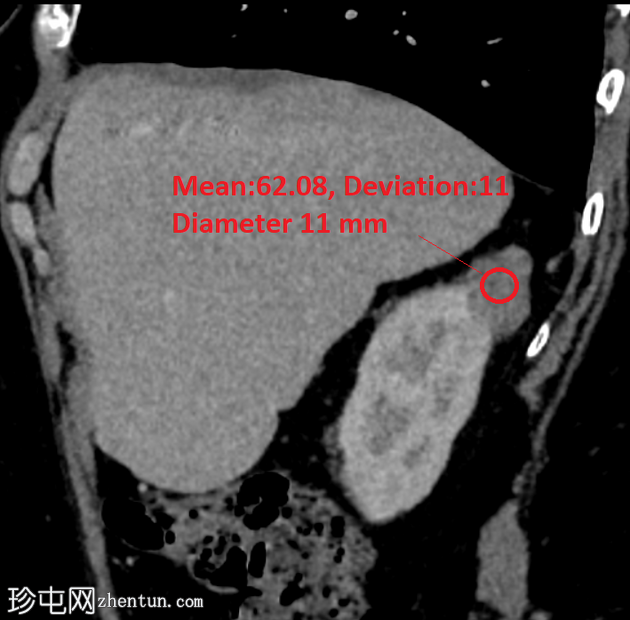

矢状位增强扫描(门静脉期)

6.png

右肾后上极可见2.8 cm外生性强化病灶,提示肾细胞癌(RCC)。右肾静脉和下腔静脉通畅。未见明显局部淋巴结肿大。右肝叶可见高密度金属影。可见含脂肪的脐疝。

嗜铬细胞肾细胞癌 (chRCC) 约占肾脏恶性上皮肿瘤的 5%,常为偶然发现。该肿瘤血管丰富度中等,但病理上血管分布不明显,在所有影像学阶段的强化程度均低于肾皮质,肾实质期强化最为显著。